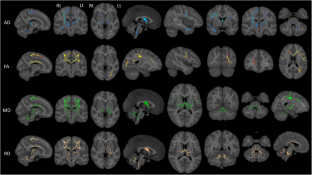

Primary lateral sclerosis (PLS) is classically considered a ‘pure’ upper motor neuron disorder. Motor cortex atrophy and pyramidal tract degeneration are thought to be pathognomonic of PLS, but extra-motor cerebral changes are poorly characterized. In a prospective neuroimaging study, forty PLS patients were systematically evaluated with a standardised imaging, genetic and clinical protocol. Patients were screened for ALS and HSP associated mutations, as well as C9orf72 hexanucleotide repeats. Clinical assessment included composite reflex scores, spasticity scales, functional rating scales, and screening for cognitive and behavioural deficits. The neuroimaging protocol evaluated cortical atrophy patterns, subcortical grey matter changes and white matter alterations in whole-brain and region-of-interest analyses. PLS patients tested negative for known ALS- and HSP-associated mutations and C9orf72 repeat expansions. Voxel-wise analyses revealed anterior cingulate, dorsolateral prefrontal, insular, opercular, orbitofrontal and bilateral mesial temporal grey matter changes and white matter alterations in the fornix, brainstem, temporal lobes, and cerebellum. Significant thalamus, caudate, hippocampus, putamen and accumbens nucleus volume reductions were also identified. Extra-motor clinical manifestations were dominated by verbal fluency deficits, language deficits, apathy and pseudobulbar affect. Our clinical and radiological evaluation confirms considerable extra-motor changes in a population-based cohort of PLS patients. Our data suggest that PLS should no longer be considered a neurodegenerative disorder selectively affecting the pyramidal system. PLS is associated with widespread extra-motor changes and manifestations which should be carefully considered in the multidisciplinary management of this low-incidence condition.